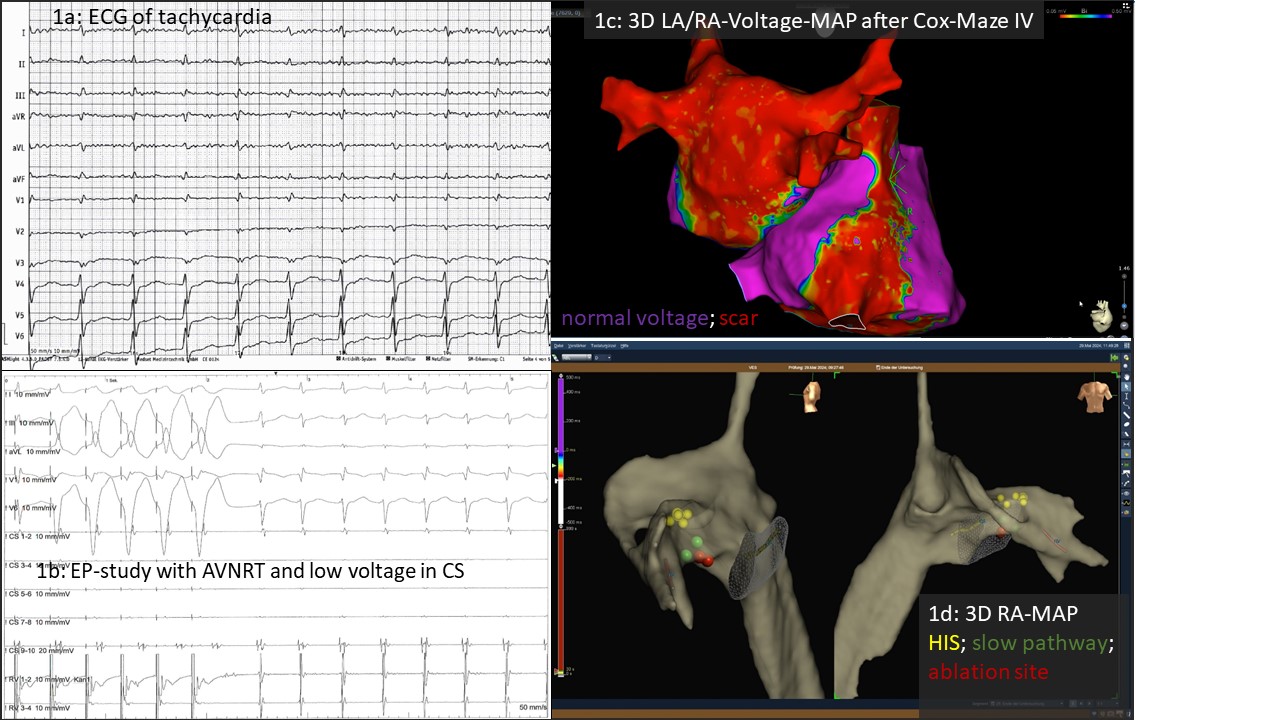

We present a 63-year-old, athletically active patient with a five-year history of highly symptomatic AF. Since 2019, he underwent six left atrial (LA) endocardial ablation procedures in high-volume centers, including pulmonary vein (PV) isolation and extensive substrate modification (three with radiofrequency, three with pulsed field ablation). During the sixth procedure, durable isolation of all PVs, a complete LA posterior box, and cavotricuspid isthmus (CTI) block were confirmed. In December 2023, a surgical biatrial Cryo Cox-Maze IV procedure was subsequently performed at our center. Following surgery, the patient still complained of exercise-induced palpitations lasting several hours (ECG Fig. 1a) and presented for touch-up ablation.

Voltage mapping after Cox-Maze IV confirmed durable PV isolation, an intact posterior LA box, complete CTI block, and a cavo-caval right atrial line (Fig. 1c). Surprisingly, programmed atrial stimulation induced typical AV nodal reentrant tachycardia (AVNRT) rather than the expected LA tachycardia (Fig. 1b). The patient identified this arrhythmia as clinically relevant. Following successful slow pathway modification (Fig. 1d), the patient continues to be free of arrhythmia.

Management of persistent LA tachyarrhythmias after multiple ablations is complex. Surgical biatrial ablation may represent a valuable option in experienced centers. This case highlights that the endocardial created tricuspid line as well as the surgical leasion up to the right atrial appendage may alter the electrophysiology of Koch’s triangle, potentially facilitating AVNRT. Thus, precise knowledge of both, the surgical and catheter-based lesions is essential for electrophysiologists performing touch-up ablations, as atrial signals can be difficult to interpret after extensive biatrial procedures. Moreover, even when only AF or LA tachycardia is suspected, programmed atrial stimulation at the beginning of the procedure may uncover alternative arrhythmia mechanisms.